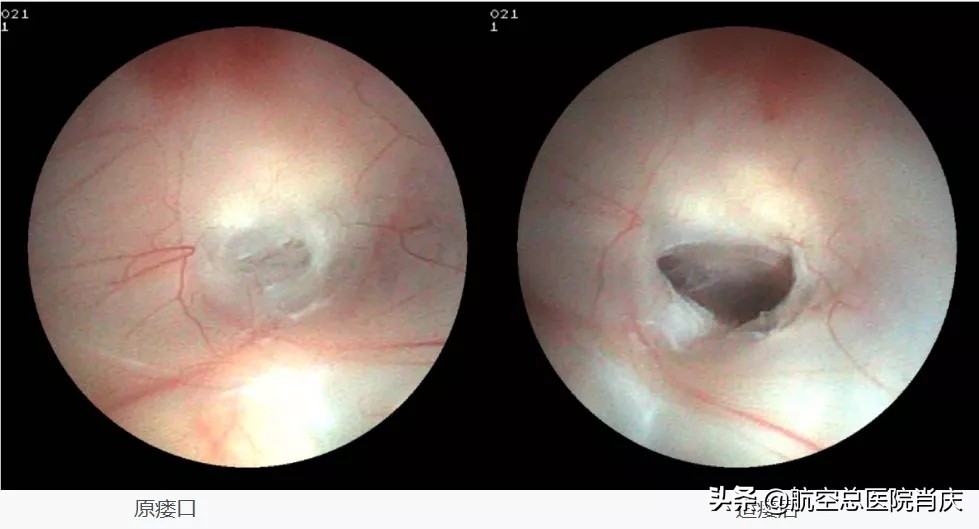

神经内镜下第三脑室造瘘术 中,瘘口位置选择更为灵活,除最常见的第三脑室底外,还可选择终板造瘘或向后选择第三脑室-小脑上池造瘘。第三脑室底造瘘术除能解除导水管梗阻,术后基底动脉的搏动直接作用于第三脑室,可以在一定程度上改变脑脊液循环动力,从而缓解脑积水。